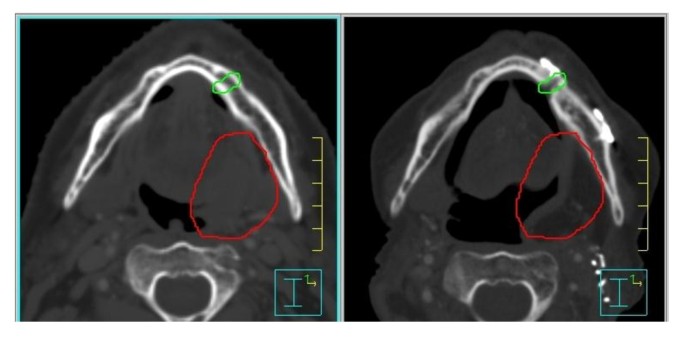

Methods

A retrospective chart review was performed for all patients who underwent a mandibulotomy for resection of oral cavity and oropharynx cancer from 2002 to 2010 at the Princess Margaret Cancer Centre (PMCC), Toronto, Canada. Institutional Ethics Review Board approval was obtained. Patients were included if they underwent a mandibulotomy, either median or paramedian, as part of their primary surgical management for oral cavity cancer or for salvage surgery of recurrent oropharynx or oral cavity cancer. Patients with incomplete charts or who were lost to follow-up were excluded. Patients were also excluded if they did not have dentition around the osteotomy site or if they underwent a mandibulectomy. Eligible patients were identified from a prospective head and neck surgical registry that included patients from 2002 to present and a retrospective oral cavity database, which included all patients undergoing management of oral cavity cancer between 1994 and 2004. A comprehensive review of all medical and available dental charts (dental charts were not available for all the patients) was performed. The data collected included socio-demographics, comorbidities, stage and location of tumour, prior dental assessment, previous treatment (surgery, radiation or chemotherapy), location of the osteotomy, whether the reconstruction plate was contoured before or after the mandibulotomy (pre or post plating), as well as complications. Radiation data collected included method of delivery (conventional vs. intensity modulated radiation therapy (IMRT)), the prescribed dose and fractionation as well as the mean dose to the mandibulotomy site. The dose at the osteotomy site was measured on the original treatment after contouring the mandibulotomy site over a width of 5 mm. For the post radiotherapy (RT) mandibulotomies, we fused postoperative computerized tomography (CT) scans with the original treatment distribution, in order to estimate the preoperative dose received by the mandibulotomy site (Figures 1 and 2).